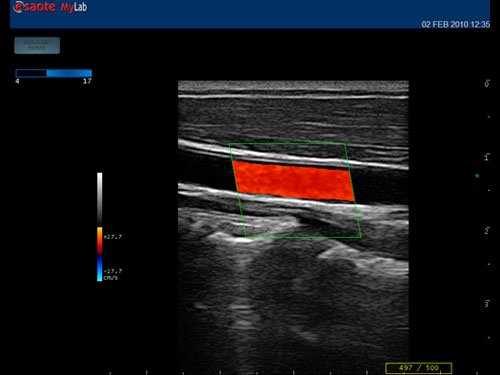

12”-Full-Touchscreen Farbdoppler

Das MyLab™One steht für das revolutionäre „Arm-held“ Hochleistungs-Ultraschallsystem mit 12”-Full-Touchscreen. Aufgrund seines geringen Gewichts und der Tragbarkeit kann es auch ohne Arbeitsfläche verwendet werden. Eine einzelne Person kann dieses Gerät aufgrund seiner einzigartigen Funktionen allein und selbstständig bedienen.

Das Ultraschallsystem MyLab™One zeigt exemplarisch den modernen Bedarf an Diagnosekapazitäten in verschiedenen Anwendungsbereichen: Radiologie, Kardiologie, Phlebologie, Frauenheilkunde, Orthopädie, Regionalanästhesie, Sportmedizin, Interventionell, Rheumatologie, Erste Hilfe, Notfallmedizin, Vaskuläre Reihenuntersuchungen, Allgemeinpraxis.

• Features: Farb/Doppler, Nadelführung, SW/B-Bild